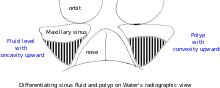

Interpretation of results

| Pathology | Observation |

|---|---|

| None (Normal) |

|

| Maxillary sinusitis[2] |  Differentiating pathology in maxillary sinus

|

| Polyp |

|

| Malignancy |

Onhgren's line